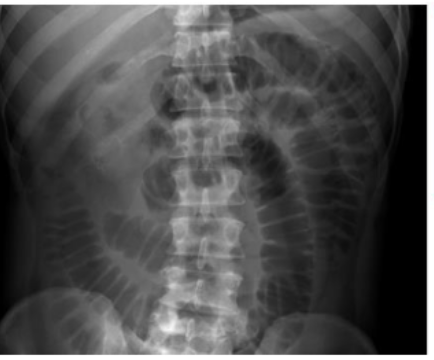

What is this and what type of scan

small bowel obstruction/ileus, abx